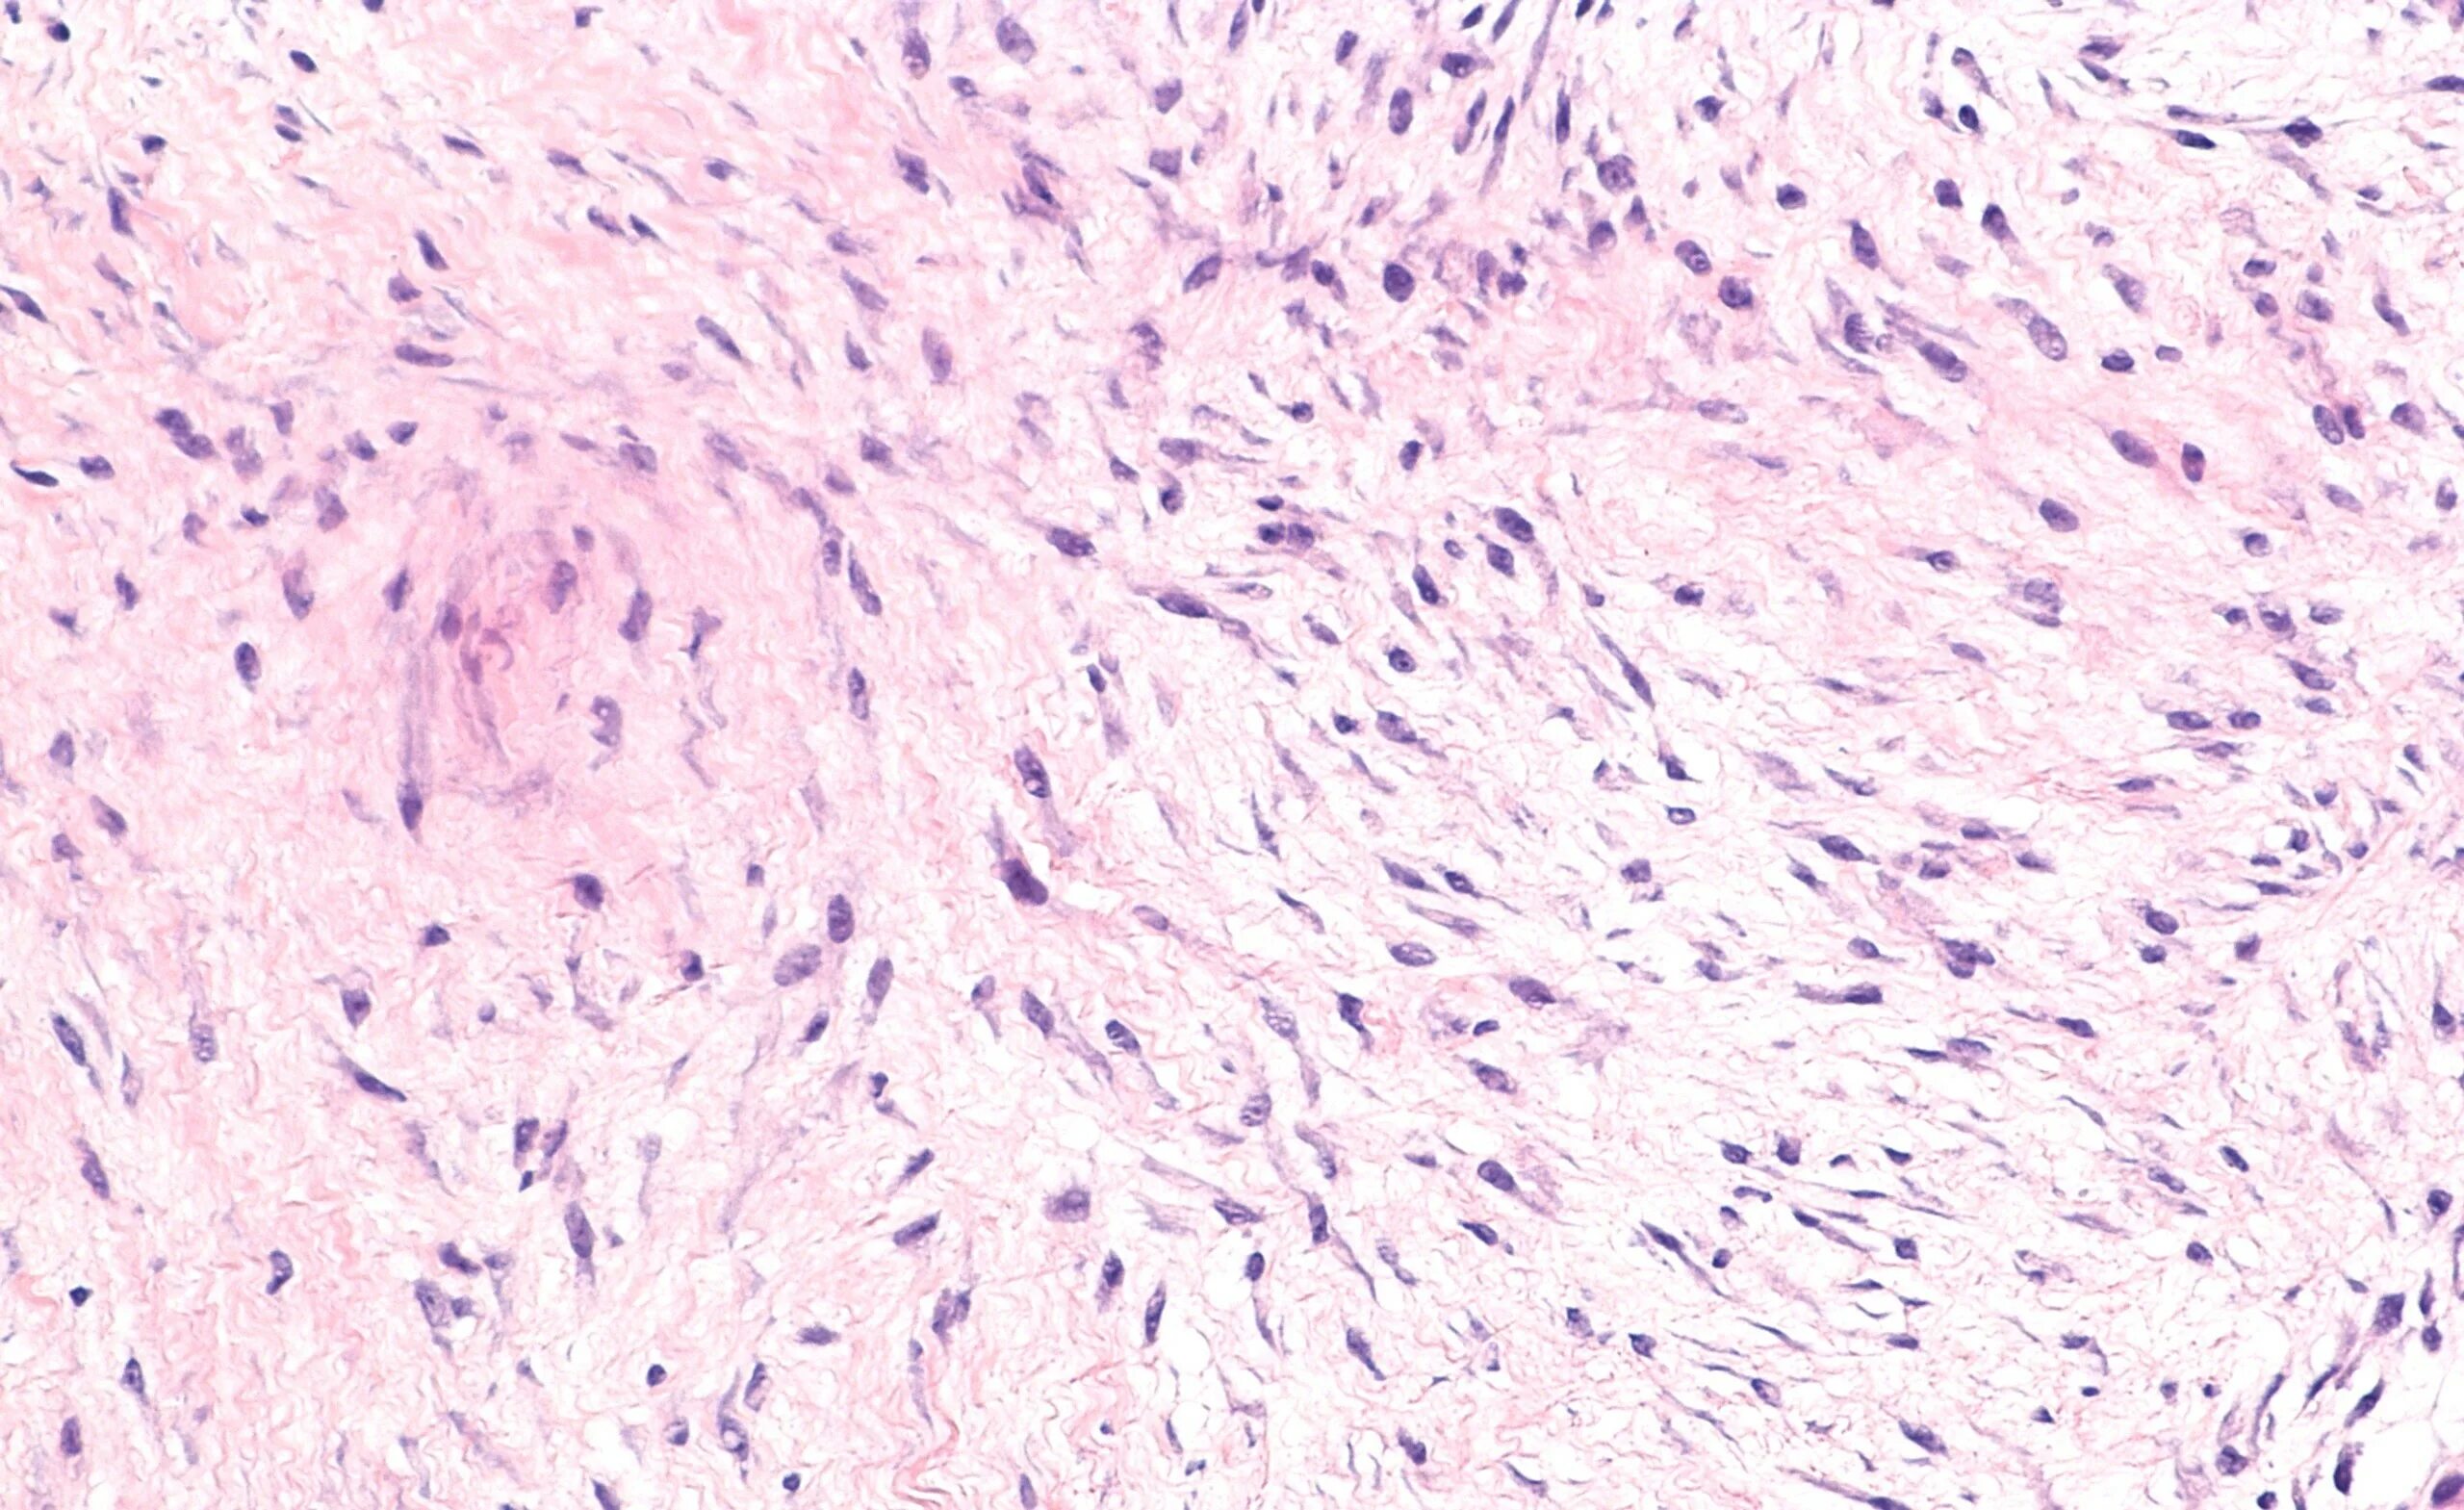

Фиброматоз мягких